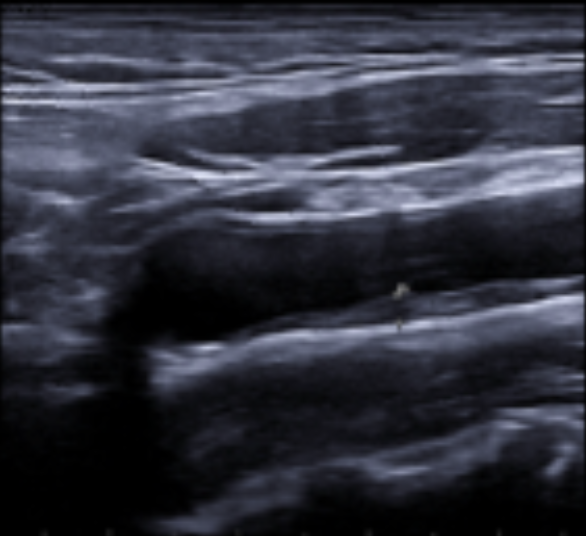

Los estudios de morbimortalidad reflejan que la enfermedad cardiovascular ocurre en más del 50% en varones y un 80% en mujeres catalogados de RCV bajo o moderado. En estudios sobre IAM el 50% de ellos presentaban uno o ningún FRCV. Así, podemos decir que existe un debate abierto sobre si las guías actuales infraestiman la arterioesclerosis ya existente, por lo que nos planteamos esta experiencia con la exploración ecográfica. Para ello realizamos una rotación en una unidad de RCV hospitalaria, con un protocolo específico para luego aplicarlo en el Centro de Salud. La valoración es similar a la utilizada en el Estudio PESA, donde se evalúa la existencia de placas de ateroma a nivel femoral, carotídeo, además de despistaje de aneurisma de aorta abdominal.

La ecografía es útil para valorar la arterioesclerosis mediante la detección de placa de ateroma en arterias carótidas y/o arterias femorales, indicando lesión de órgano diana (LOD) y llevándonos a facilitar la decisión de intensificar el tratamiento y así poder modificar la progresión de la enfermedad.